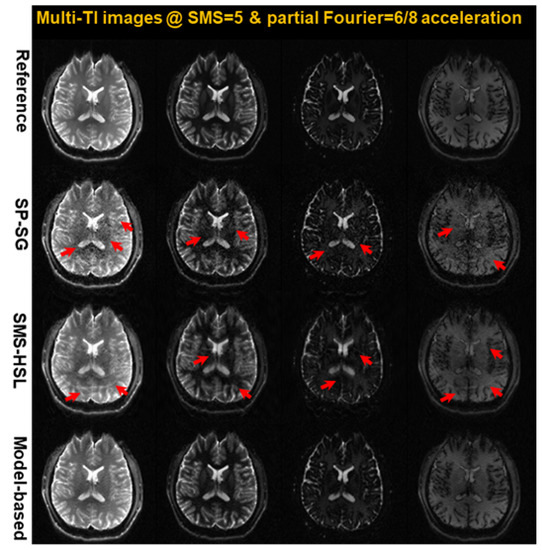

Model-Based Simultaneous Multi-Slice (SMS) Reconstruction with Hankel Subspace Learning for Accelerated MR T1 Mapping

by Sugil Kim, Hua Wu and Jae-Ho Han

Mathematics 2023, 11(13), 2963; https://doi.org/10.3390/math11132963 - 3 Jul 2023

Herein, we propose a novel model-based simultaneous multi-slice (SMS) reconstruction method by exploiting data-driven parameter modeling for highly accelerated T1 parameter quantification. We assume that the predefined slice-specific null space operator remains invariant along the parameter dimension. We incorporate the parameter dimension into [...] Read more.

Herein, we propose a novel model-based simultaneous multi-slice (SMS) reconstruction method by exploiting data-driven parameter modeling for highly accelerated T1 parameter quantification. We assume that the predefined slice-specific null space operator remains invariant along the parameter dimension. We incorporate the parameter dimension into SMS-HSL to exploit Hankel-structured and Casorati matrices. Given this consideration, the SMS signal is reformulated in k-p space as a constrained optimization problem that exploits rank deficiency for the Hankel-structured matrix and a finite-dimensional basis for a subspace containing slowly evolving signals in the parameter direction. The proposed model-based SMS reconstruction method is validated on in vivo data and compared with state-of-the-art methods with slice acceleration factors of 3 and 5, including an in-plane acceleration factor of 2. The experimental results demonstrate that the proposed method performs effective slice unfolding and signal recovery in reconstructed images and T1 maps with high precision as compared to the state-of-the-art methods. Full article